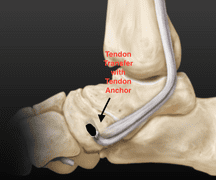

Tend on Transfers

Tendon transfer procedures are typically reserved for flexible flat feet, in cases where the tendon that is in charge of supporting the arch(posterior tibial tendon) is compromised, and as a result the foot becomes flat. In these cases the tendon is repaired and rerouted into a position where it can better support the arch. In some cases the repair is augmented by transferring a nearby tendon to reinforce the arch. In most flat foot surgeries a sole tendon transfer procedure is not sufficient and is combined with bony procedures.